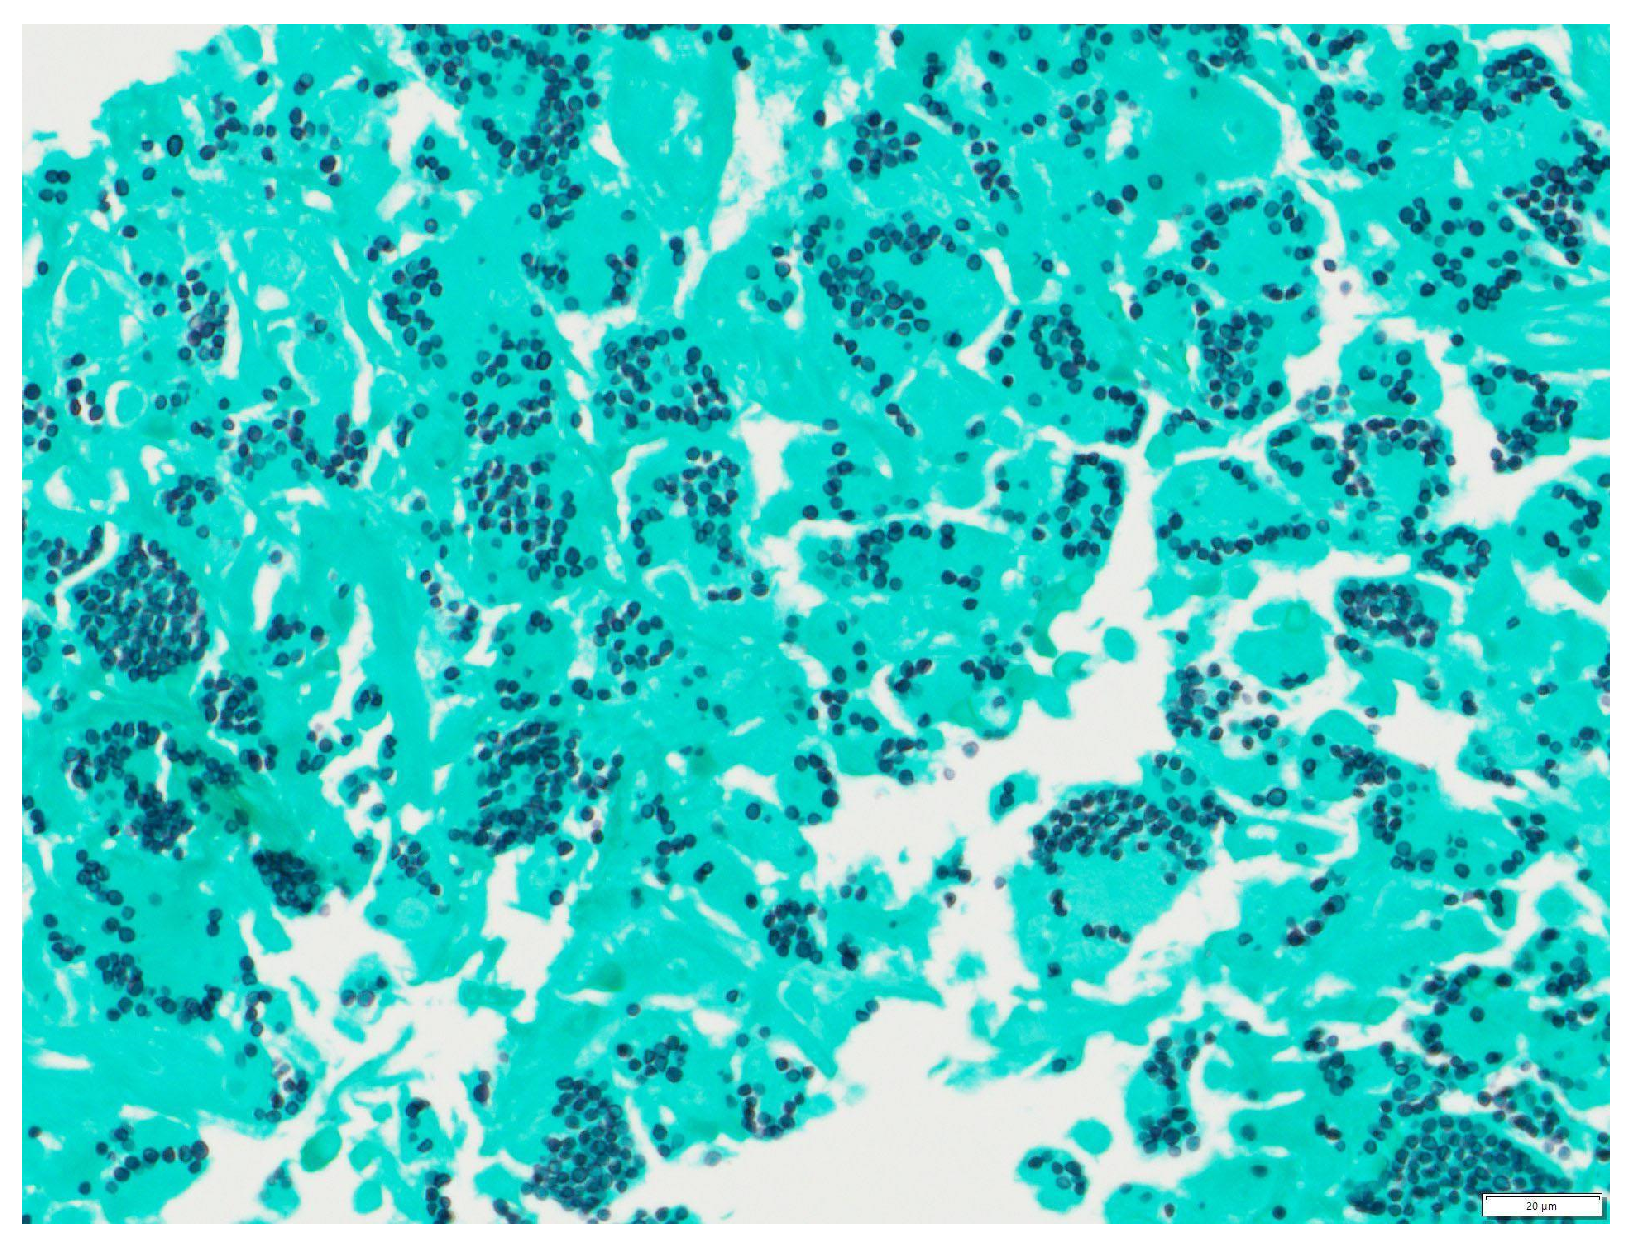

Figure 6. Tongue punch biopsy: Histoplasmosis 400× GMS. Grocott methenamine silver (GMS) stain highlighting Histoplasma cell walls within histiocytes.

The tongue findings prompted a contrasted CT of the neck and soft tissue without significant findings. The patient underwent a punch biopsy of the lingual nodular lesion and a CT-guided left adrenal mass biopsy. Yeast forms compatible with Histoplasma were observed. On the histopathology, fungal organisms consistent with Histoplasma species and necrotizing granulomatous inflammation with elements compatible with Histoplasma were seen involving both the lingual and adrenal masses, see Figure 3, Figure 4, Figure 5 and Figure 6. These findings prompted an infectious disease (ID) consultation. Upon speaking to the family, the patient had reported episodes of confusion prior to admission, therefore, an MRI of the brain with and without contrast was obtained that showed a sub-centimeter enhancing focus within the left putamen/external capsule junction with mild edema.